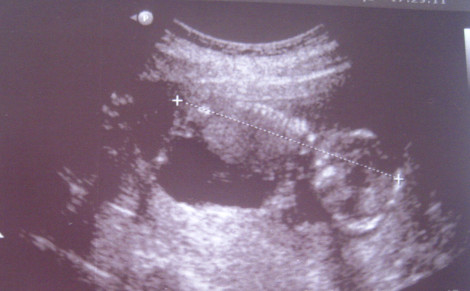

W 15 tygodniu ciąży dziecko ma około 11 centymetrów. Ważyć może od 56 do 85 gramów. Maluszek jest już jak średnia pomarańcza. Już na tym etapie płód wyglądem przypomina małe dziecko. Uszy ma na swoim miejscu (po bokach twarzy), wędrówkę zaczynają też oczy, które z tyłu twarzy przemieszczają się na przód twarzy.

Dziecko już sprawnie się porusza. Jego ruchy są skoordynowane, świadome, dziecko już nad nimi panuje, choć nadal musi sporo ćwiczyć, dlatego wykorzystuje w tym celu każdą chwilę. Nie próżnuje… W każdej minucie uczy się własnego ciała, próbuje nowych rzeczy i doskonali już zdobyte umiejętności. To się zaczyna opłacać, bo mięśnie nóg i rąk są silne. Maluszek umie nawet już ssać kciuk, a także oddychać, wie, w jaki sposób wykonuje się ruchy klatki piersiowej. Ta umiejętność pozwoli mu przeżyć, gdy będzie musiał zaczerpnąć pierwszego powietrza.